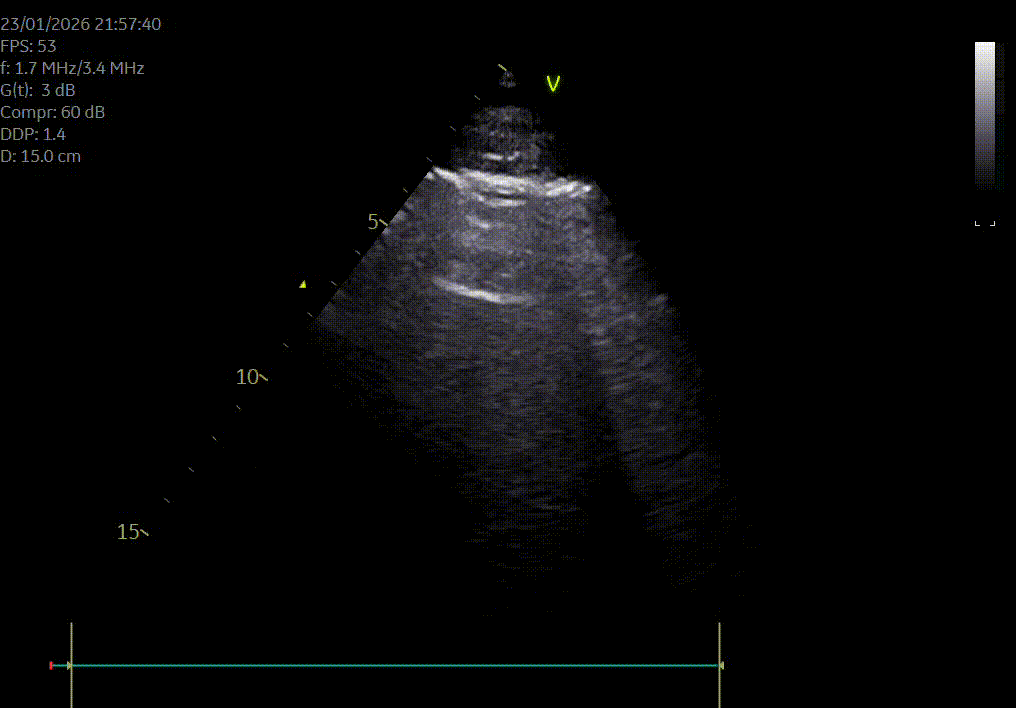

Heeft uw hond of kat een hartruis? Het is dan aangewezen om een echocardiografie (hartfilmpje) uit te laten voeren om na te gaan of er best ondersteunende hartmedicatie moet opgestart worden. Met een echocardiografie gaan we na of het hart normaal gevormd is, normaal werkt en beoordelen we de ergheidsgraad van eventuele kleplekken.

Hartonderzoek - Echocardiografie - Electrocardiografie (EKG) - Radiografie